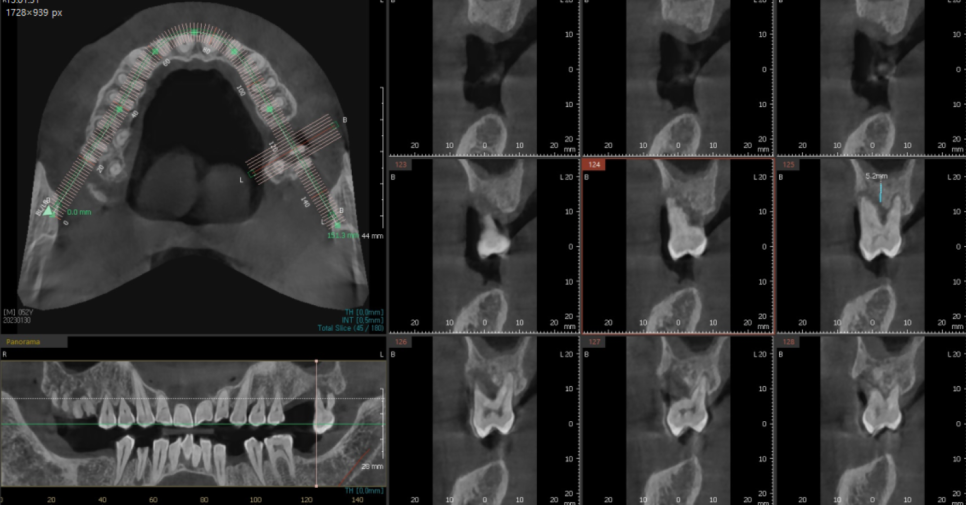

어금니 빠짐 부분을

3차원적으로 분석을 하고

치료 계획을 세워드렸습니다.

미리 ct를 통해 분석하고 수술을 해서